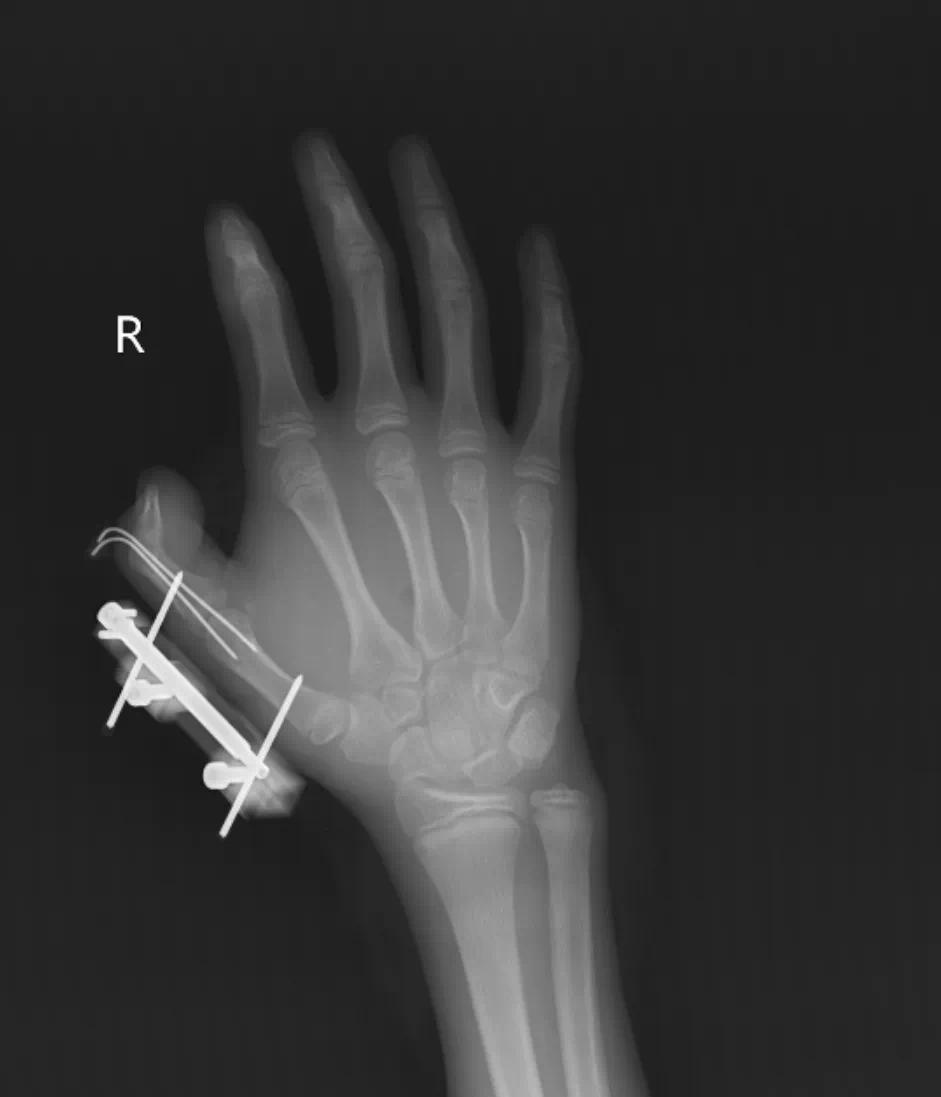

(术后X线检查显示骨折复位良好)

见状,家人赶紧带他到当地医院包扎,随后紧急转往湖南省人民医院手足显微外科。医院立即开通绿色通道,手术团队连夜进行清创、复位脱位的掌指关节、固定骨折、逐层修复肌肉。经过 7 天的精心护理,维维的拇指总算保住了,但后续还需要长期康复训练,才能慢慢恢复手部精细动作功能。